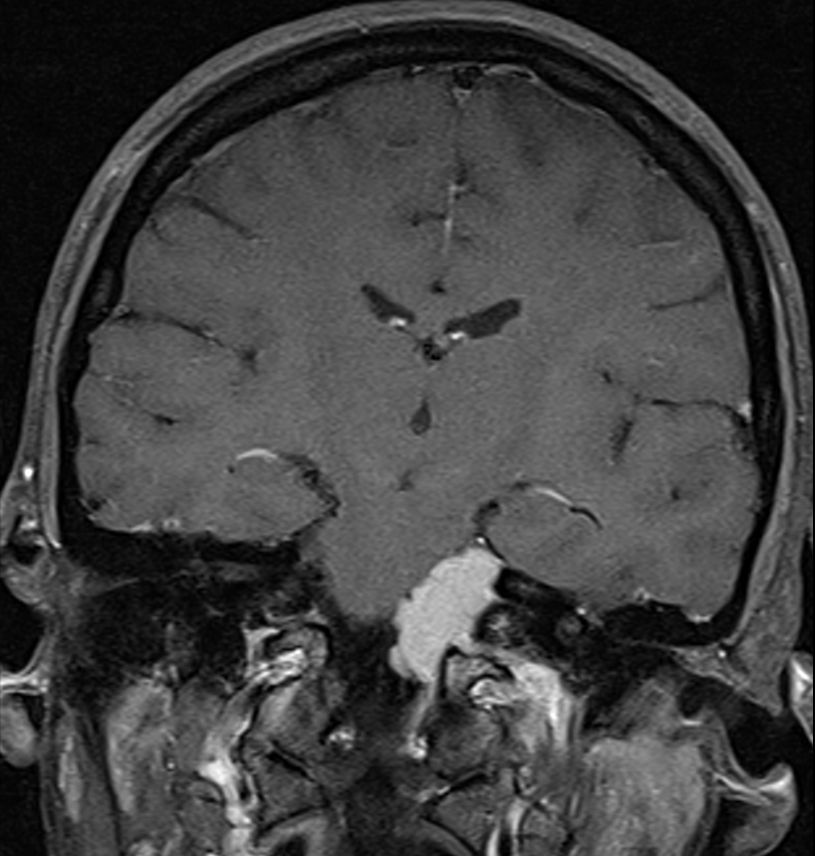

| Meningeom frontobasal |

Asymptomatisch. Geringe Größenzunahme nach einem Jahr. OP geplant.